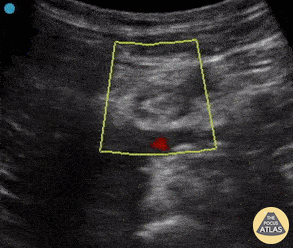

Vascular - Common Femoral DVT

A 65 yo male presented with 2 week hx of proximal left LE pain. Pt denied trauma or risk factors for VTE. Also did not have visible abnormalities on clinical exam. Seen here is POCUS of his common femoral vein; note the hyperechoic thrombus and absent blood flow (when compared to adjacent femoral artery). This vein was also non compressible. This case highlights that even with low pre-test probability, POCUS can help drive ones differential diagnosis! Mandy Peach, MD @mandy_peach Saint John Regional Hospital. NB, Canada